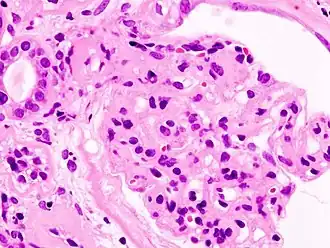

Гистопатологическая картина диабетического гломерулосклероза с нефротическим синдромом.

Гистопатологическая картина диабетического гломерулосклероза с нефротическим синдромом. Другой почечный клубочек.